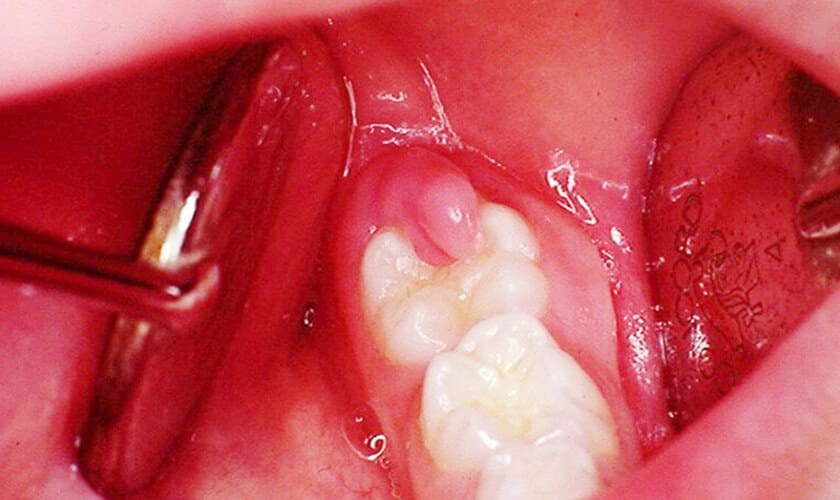

Mọc răng khôn

Răng khôn mọc là một quá trình tự nhiên. Tuy nhiên, đôi khi sự thay đổi này có thể khiến nướu bị sưng tấy. Nướu răng khôn bị sưng khi vẫn còn ở dưới nướu. Khi răng khôn trồi lên chúng sẽ tạo ra khoảng trống để vi khuẩn có thể xâm nhập vào nướu và dẫn đến sưng đau.

- Nếu viêm nướu ở phần trong cùng của răng do răng khôn mọc lệch, mọc ngầm: Bác sĩ sẽ dùng kết quả chụp x-quang để xác định nguyên nhân, hướng mọc và kích thước của răng khôn. Bác sĩ sẽ gây tê và nhổ răng khôn bằng công nghệ mới. Sau điều trị, vùng nướu sẽ không sưng đau nữa